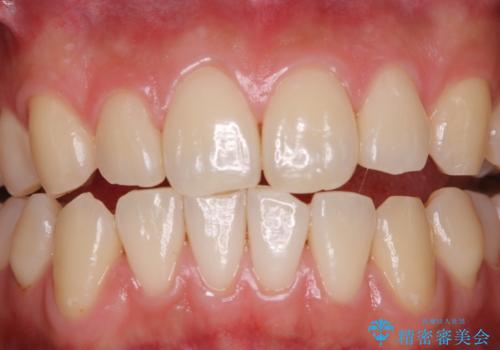

日々の磨き残しをPMTCできれいに

歯垢染色液を使うと、一見きれいな歯でも染まっている所が全て歯垢(プラーク)なのがはっきり分かります。歯に付着した歯垢(プラーク)は肉眼では認識しにくいものです。完璧に磨けているつもりでも、磨き残しが残っているかもしれません。

毎日の歯磨きだけでは、隅々までキレイに磨くことは困難です。さらに、体調不良や疲労などで免疫が低下しているとお口の中の細菌が増えやくなることがあります。

そのため、歯科医院にて定期的に歯磨きのチェックや専門的な機械でのクリーニングをすることが大切です。